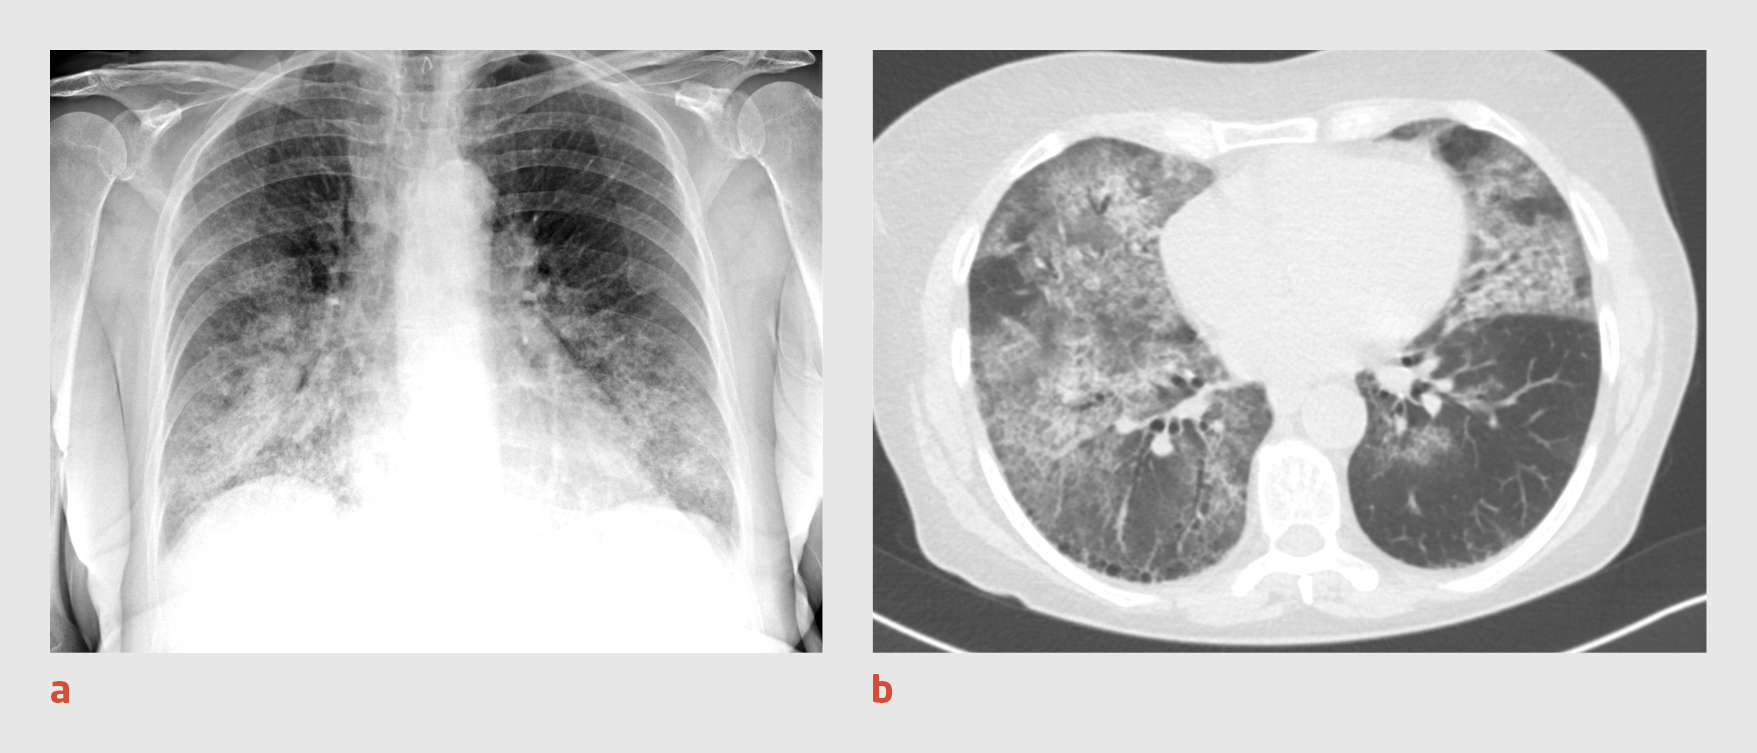

Patiënt A, een 30-jarige man die bekend is met middelenmisbruik (alcohol, amfetamine, cannabis en cocaïne), bezoekt de Spoedeisende Hulp, omdat hij sinds enkele dagen hoest en toenemend kortademig is. Bij lichamelijk onderzoek zien wij een niet-acuut zieke man met koorts en een zuurstofsaturatie van 99%, terwijl zuurstof wordt toegediend met 5 l/min. Bloedonderzoek geeft de volgende uitslagen (referentiewaarde tussen haakjes): lymfocytengetal: 1,48 x 109/l (1-3,5); CRP: 71 mg/l (< 10); natrium: 126 mmol/l (135-145); en LDH: 678 U/l (< 250). De thoraxfoto toont een ‘moppig’ beeld met diffuus verspreide consolidaties in beide longen, passend bij een atypische pneumonie (figuur 1a). Vanwege het vermoeden van covid-19 wordt patiënt opgenomen in strikte isolatie.

Figuur 1

Thoraxfoto en CT-thorax van patiënt A

Figuur 1 | Thoraxfoto en CT-thorax van patiënt A

(a) Thoraxfoto van een 30-jarige man waarop een ‘moppig’ beeld te zien is met diffuus verspreide consolidaties in beide longen, passend bij een atypische pneumonie. (b) Op de CT-scan van de thorax zijn in beide longen diffuus verspreide matglasafwijkingen en consolidaties zichtbaar, overeenkomstig een CO-RADS-score van 5.

Er wordt een PCR-test verricht op SARS-CoV-2 in materiaal uit de nasofarynx en patiënt wordt intraveneus behandeld met ceftriaxon 2 g 1 dd. De volgende dag blijkt de uitslag van de PCR-test negatief te zijn. Omdat wij nog steeds een sterk vermoeden van covid-19 hebben, wordt opnieuw een PCR-test verricht. Ook wordt er een CT-scan van de thorax gemaakt, waarop in beide longen diffuus verspreide matglasafwijkingen en consolidaties worden gezien (CO-RADS-score 5) (figuur 1b). Patiënt blijft zuurstofbehoeftig en wordt behandeld met chloroquine.